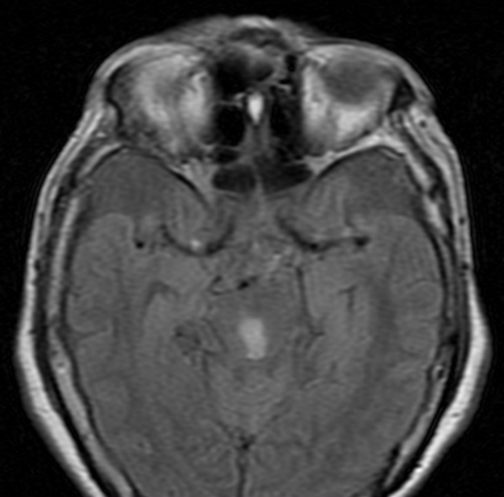

TAC de cráneo simple sin lesiones agudas, RM cerebral con imagen hiperintensa en difusión, hipointensa en ADC e hiperintensa en FLAIR a nivel de tegmento mesencefálico medial (ver imagen 2), compatible con infarto mesencefalico en etapa subaguda, no candidata a trombolisis, se realizaron estudios de factores de riesgo cardiovascular sin hallazgos significativos, se dio egreso con prevencion secundaria.

Imagen 2. RM cerebral en secuencia difusión, ADC y FLAIR